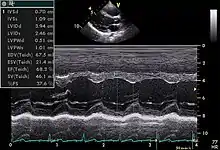

مد حرکتی (Motion mode)

این روش برای بررسی ارگانهای متحرک در بدن استفاده شده و امکان تعیین سرعت ارگان را فراهم میکند.در این روش با ارسال پالسهای سریع فراصوت و اسکن یک خط از بافت، اکوهای دریافتی از هر خط بر حسب زمان نشان داده میشود.برای تشکیل تصویر میتوان از مد دامنه یا از یک خط تصویر مد روشنایی استفاده نمود. از کاربردهای این روش بررسی ماهیچه و دریچههای قلب میباشد.